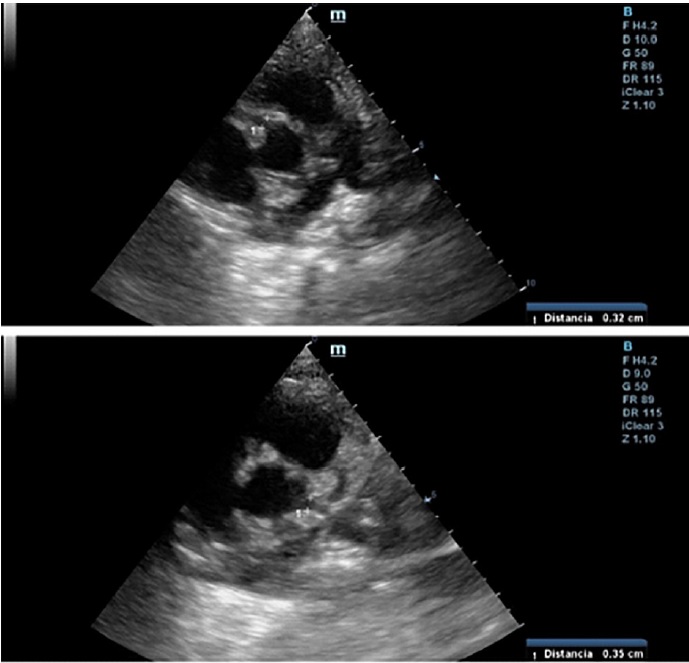

A las 24 horas del alta presenta registro febril, regular estado general, acompañado de lengua aframbuesada, edema bipalpebral y conjuntivitis. Se interna. Por laboratorio se constatan parámetros de inflamación, IgG para SARS-CoV 2 positivo y al repetir ecocardiograma Doppler (Figura 1) presenta dilatación aneurismática de ambas coronarias con función ventricular conservada (Tabla 1, se detallan los valores de las coronarias con sus respectivos Z score, en los sucesivos controles ecocardiográficos). Se reasume el cuadro como SIM-C. Recibe tratamiento inmunomediado y antiagregante plaquetario con gammaglobulina (2 gr/kg/dosis), metilprednisolona (10 mg/kg/dosis, 3 pulsos), AAS 5 mg/kg/día. Presenta leve mejoría clínica y analítica. El control cardiológico a los 5 días revela similares características. Se lo clasifica como resistente al tratamiento y se indica Infliximab (5 mg/kg). Evoluciona favorablemente, con marcada mejoría clínica y cardiovascular; se otorga el alta luego de 16 días. Se programa control cardiológico y reumatológico más tratamiento antiagregante y antiinflamatorio.

Ecografía Doppler 2D

Fig. 1 Ecocardiograma Doppler 2D (eje corto de los vasos): se observa coronaria derecha en la parte superior, y coronaria izquierda en la inferior.